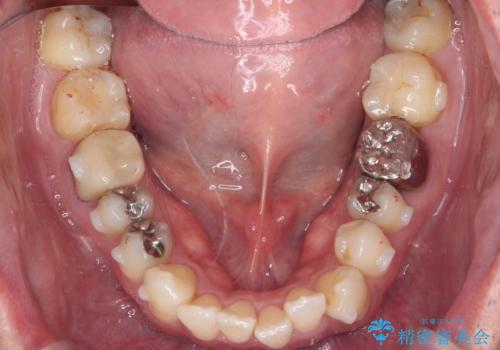

矯正と虫歯のセラミック治療 総合歯科治療の実践

- 突き出た前歯の角度の改善と虫歯治療の改善を求めて来院されました。

虫歯を除去したのち、マウスピース矯正治療を行い、歯並びやがたつきを改善したのち、セラミックに置き換えることで審美性の向上を計画します。